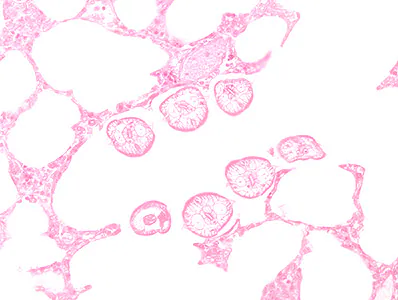

A lung biopsy was obtained on a 29-year-old-patient from Cameroon with cough, dyspnea, and hemoptysis. Figures A–D show what was observed on a hematoxylin and eosin (H & E) stained section; Figure A is at 200x, Figure B 400x, and Figures C and D at 1000x magnification. What is your diagnosis? Based on what criteria?

Figure A